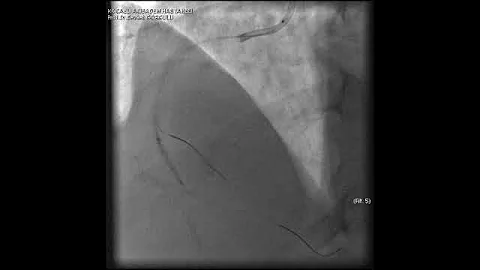

Distal Lad/d3 Bifurcation Pci Via Lima

64-year-old male with prior CABG presented with CCS Class III angina, HFrEF, multivalvular disease and positive stress MPI for ...